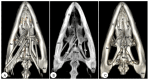

Anatomical Description of Loggerhead Turtle (Caretta caretta) and Green Iguana (Iguana iguana) Skull by Three-Dimensional Computed Tomography Reconstruction and Maximum Intensity Projection Images

The growing interest in reptiles has posed a challenge to veterinary clinicians due to the lack of a standardized system to perform anatomical studies similar to those used for dogs and cats. In this paper, we have attempted to describe, employing computed tomography and subsequent three-dimensional reconstructions, the normal anatomical features that comprise the skulls of two species of reptiles: the loggerhead turtle (Caretta caretta) and the green iguana (Iguana iguana). Computed tomography (CT) and subsequent image processing allowed the identification of the bony structures that comprise the head of these species. As a result, and based on previous articles, we propose the most significant anatomical differences and similarities between these species.